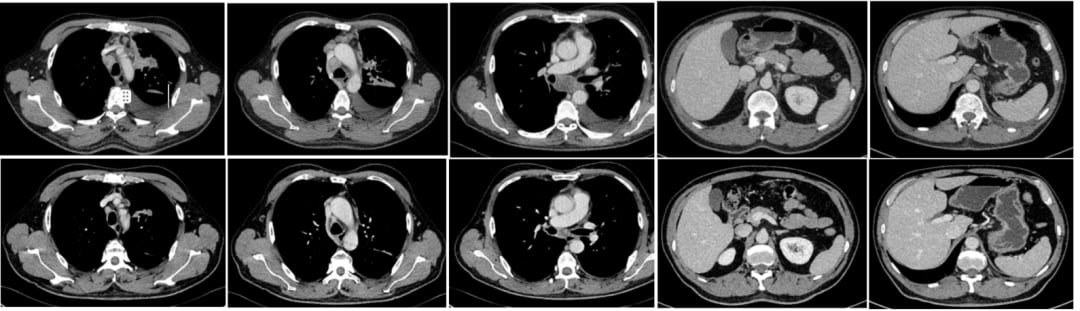

基于基因检测结果,患者于2025年6月开始口服第三代EGFR-TKI——伏美替尼(Furmonertinib)80mg,每日一次。治疗仅仅两个月后,2025年8月11日复查CT显示,患者左肺上叶及肺门区的软组织肿块明显范围局限,双锁骨区、纵隔、肺门、横隔区、腹腔、腹膜后等多发肿大淋巴结均较前缩小,这些都提示肿瘤病灶得到了显著控制。在此期间,患者未出现皮疹、腹泻、肝肾损害等常见不良反应,治疗效果令人满意,为患者带来了巨大的信心。

正当患者和家属沉浸在治疗成功的喜悦中时,挑战不期而至。在伏美替尼治疗有效期间,患者因出现呼吸系统症状就诊。复查CT提示,双肺出现了多发、新发的磨玻璃斑片,高度怀疑是间质性肺炎。结合临床症状、影像学特征,以及排除感染等其他可能原因(气管镜检查及肺泡灌洗液NGS均未见细菌、真菌、病毒等感染),患者被诊断为EGFR-TKI相关性间质性肺炎。

2025年9月,患者开始口服阿美替尼(Aumolertinib),同时辅以口服泼尼松(Prednisone)进行预防性管理,并逐渐减量停药。仅仅服药一个月后复查CT,令人欣喜的结果出现了:双肺的间质性肺炎病灶较前明显吸收!患者的病情持续稳定,截至目前已连续服用阿美替尼5个月,且实现了长达8个月的无病情进展(PFS),生活质量良好。